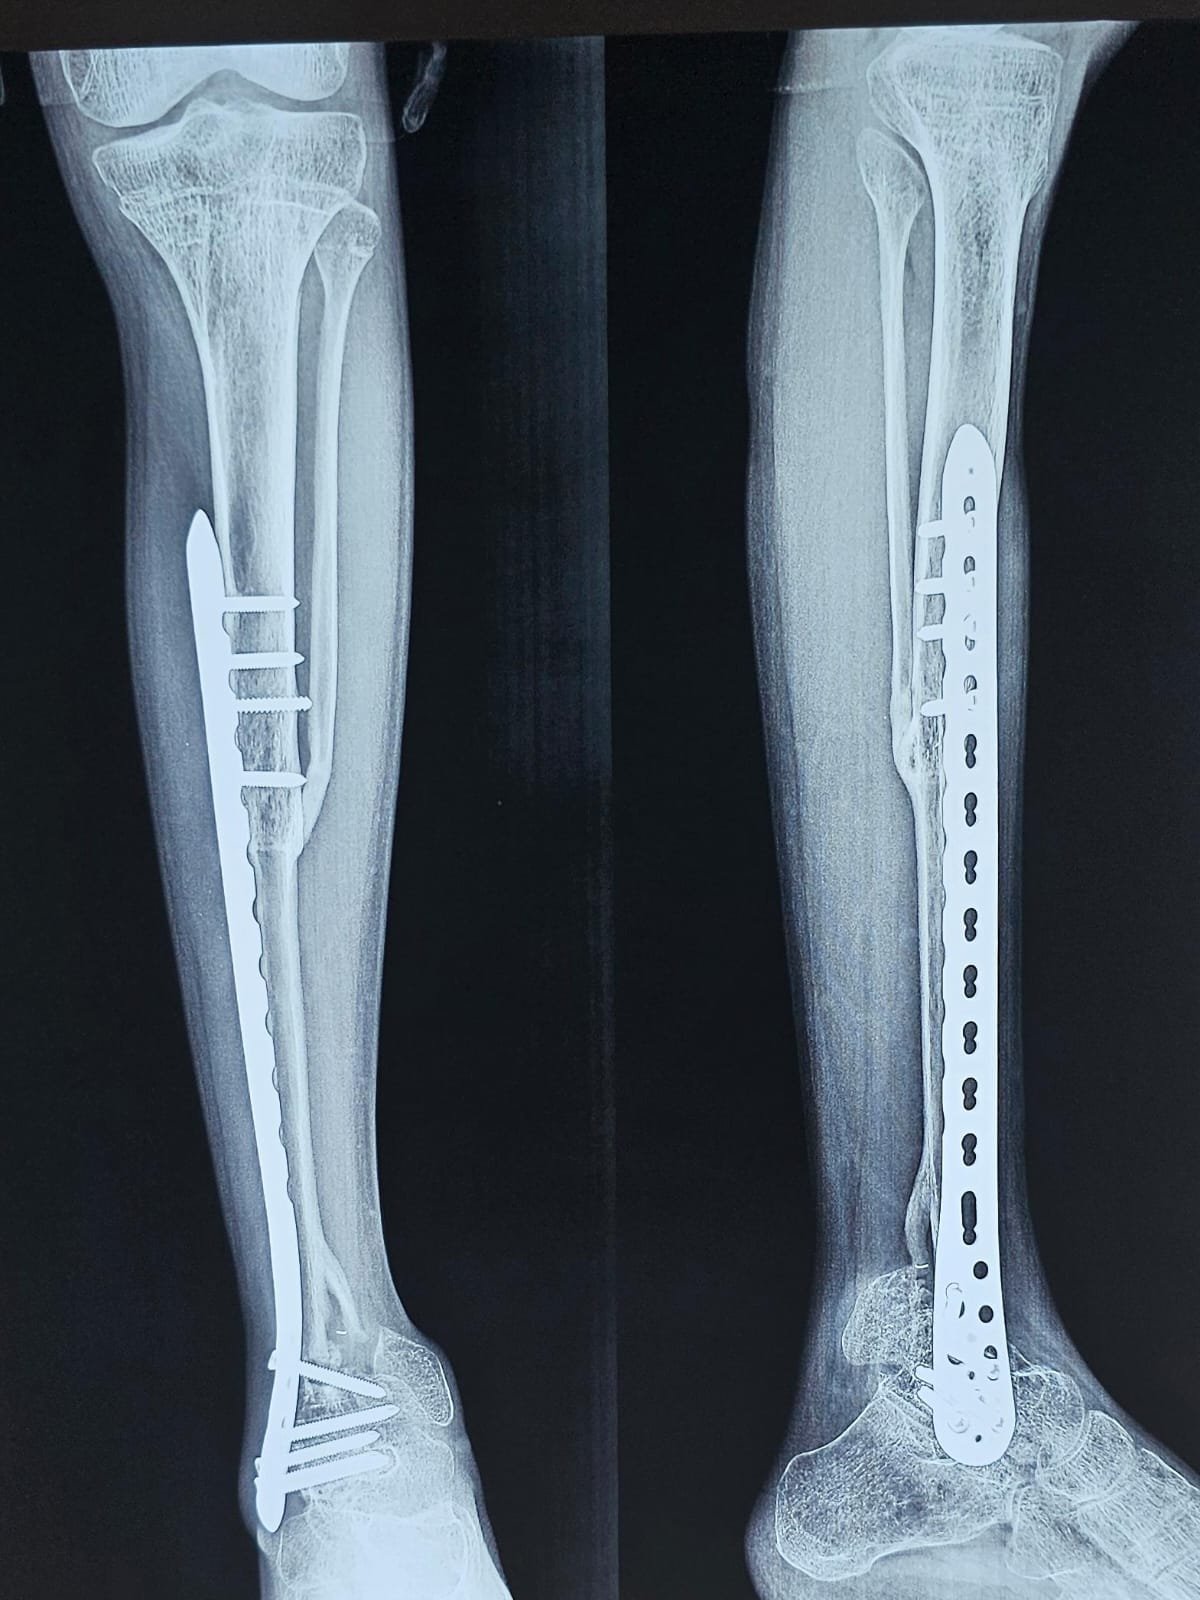

Osteosarcoma Distal Tibia

Young boy had osteosarcoma distal tibia who underwent a successful limb saving surgery more than 2 years ago using Biological reconstruction with bone transplant to save the limb. Biological reconstructions techniques are great tool to save the limb.